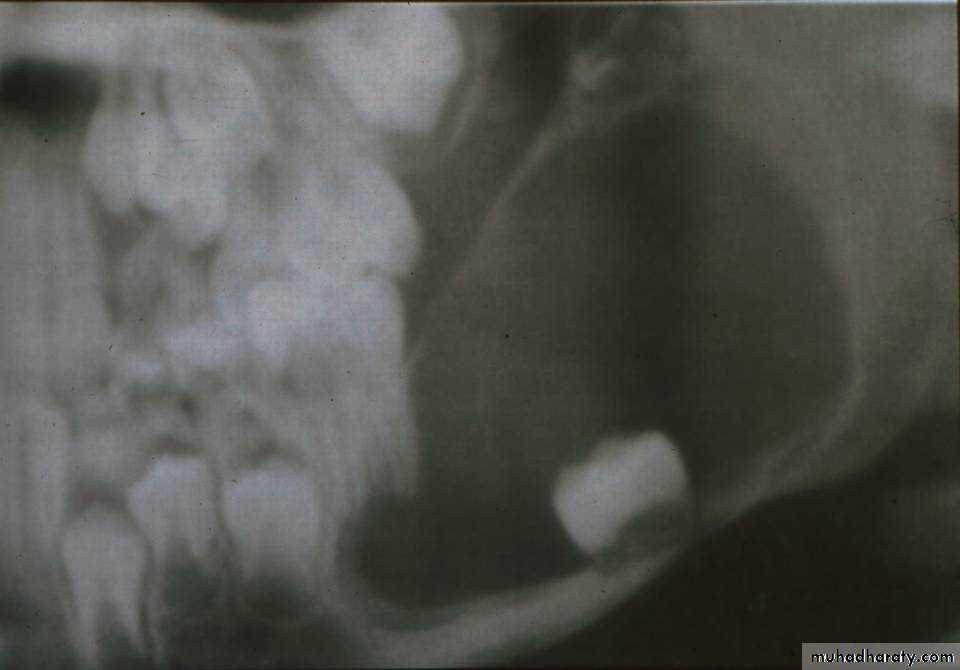

• CEOTs occur as radiolucent lesions with/without opaque foci.

• They are usually well-circumscribed and may be unilocular or multilocular.• Slightly over 50 % of the CEOTs are associated with an unerupted tooth.

Calcifying Epith. Odontogenic TumorRadiographical features